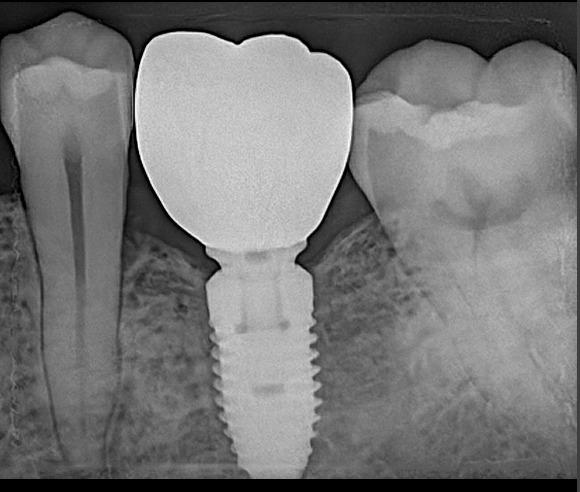

Single dental Implant

Single tooth implant most common procedure in dental practice fir single missing tooth. We ensure high quality dental Implant with high success rate. Treatment time 3 to 6 months.

Implant Gallery